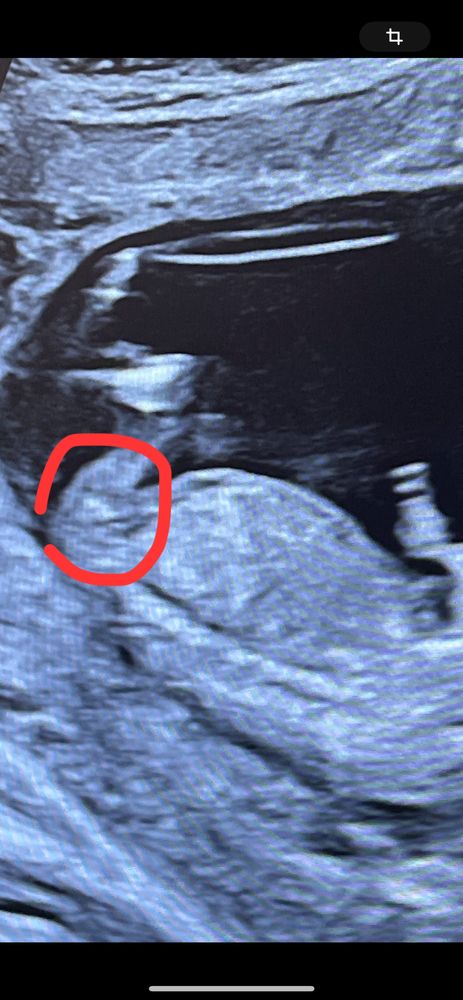

Тут не видно, половой бугорок на этом снимке узи не просматривается

Айсо, ну здравствуйте! Каким образом его может быть видно сквозь ноги? У вас же ребёнок не прозрачный 😄Это просто тень на снимке, но точно не половой бугорок)

Айсо, посмотрела, но тоже нет того ракурса на снимка, ребёнок прячет всё. Потерпите немного, скоро всё узнаете)

Но если нет сил терпеть до 2 скрининга, можно сходить платно на узи по определению пола)